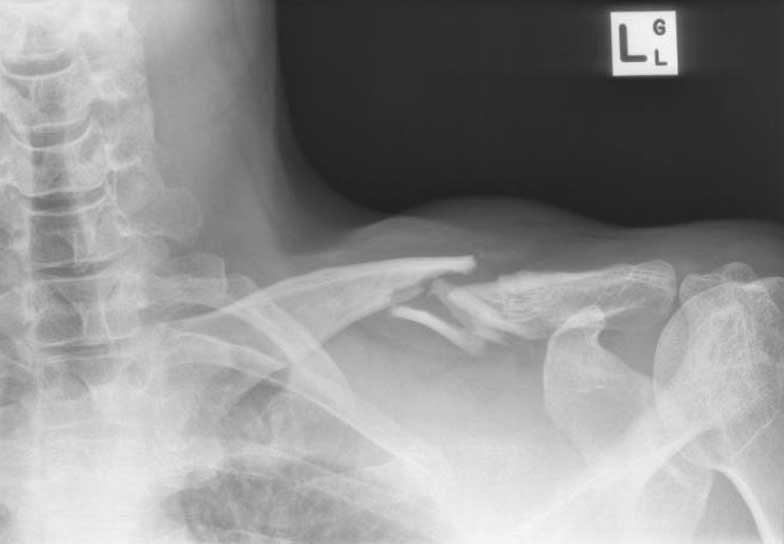

A 15 year old female fell from her pushbike causing a displaced left mid-shaft clavicular fracture. Seen 5 days later, plate & screws inserted 2 days later.

Image

DIsplaced fracture before surgery

DIsplaced fracture after surgery

Move the slider to compare before surgery and after surgery